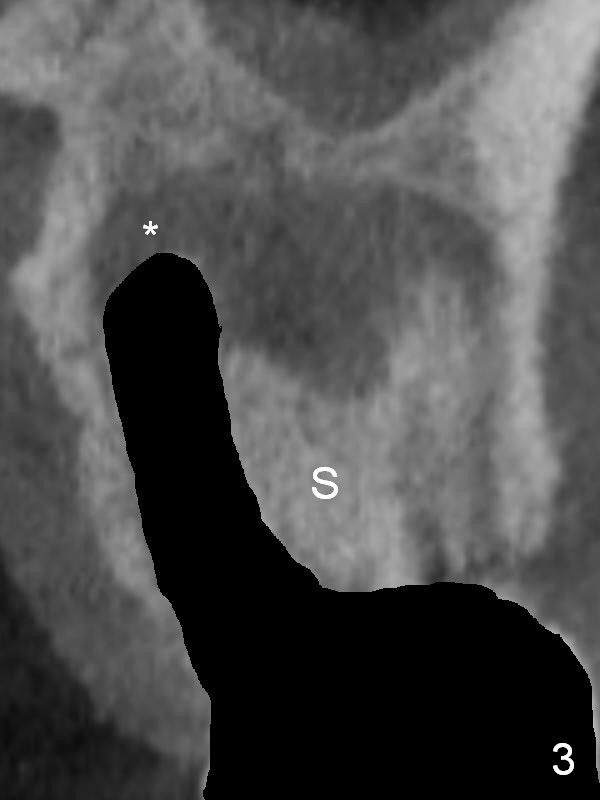

There is purulent discharge from the mesiobuccal fistula (Fig.1 <) during the tooth #14 extraction. Fig.2 is a coronal section of CBCT of the affected tooth showing a large apical lesion (*). When the tooth is removed (Fig.3), limited amount of granulation tissue is removed apical to the palatal root (P in Fig.2). The granulation tissue (Fig.4 red area) above the septum (Fig.3 S) is thoroughly extirpated when the septum is removed (Fig.5 black area).